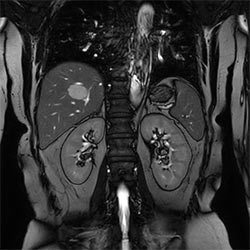

Hedefimiz, görüntü kalitesinden ödün vermeden tarama süresini kısaltmak”

Sabine Sartoretti, MD, Nöroradyoloji Bölüm Başkanı, Radyoloji ve Nükleer Tıp Fakültesi, Kantonsspital Winterthur, İşviçre